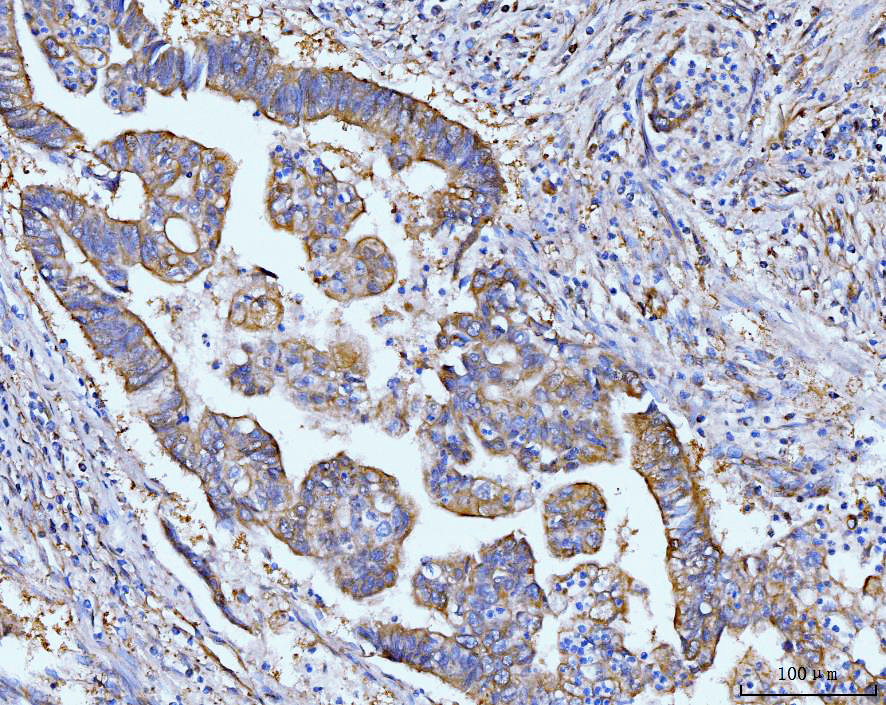

IHC analysis of GRP75/HSPA9 using anti-GRP75/HSPA9 antibody (M02561-2).

GRP75/HSPA9 was detected in a paraffin-embedded section of human gastric cancer tissue. Biotinylated goat anti-mouse IgG was used as secondary antibody. The tissue section was incubated with mouse anti-GRP75/HSPA9 Antibody (M02561-2) at a dilution of 1:200 and developed using Strepavidin-Biotin-Complex (SABC) (Catalog # SA1021) with DAB (Catalog # AR1027) as the chromogen.